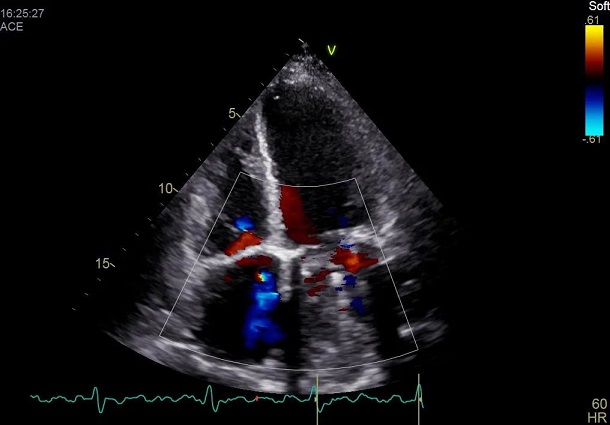

患者自述于其他医院诊断为扩张型心肌病,为进一步确认病情,吉心影像科医生为于女士进行了细致的检查。患者心电图结果显示心律失常,心房颤动,心脏彩超结果显示全心增大,二尖瓣回声增强增厚,瓣叶开放略受限,瓣叶关闭对合不良,三尖瓣开放幅度正常,关闭对合不良,左室及右室运动幅度减低。心脏超声结果显示二尖瓣关闭不全、三尖瓣关闭不全、左室收缩及舒张功能减低,右室收缩及舒张功能减低。

术前彩超影像